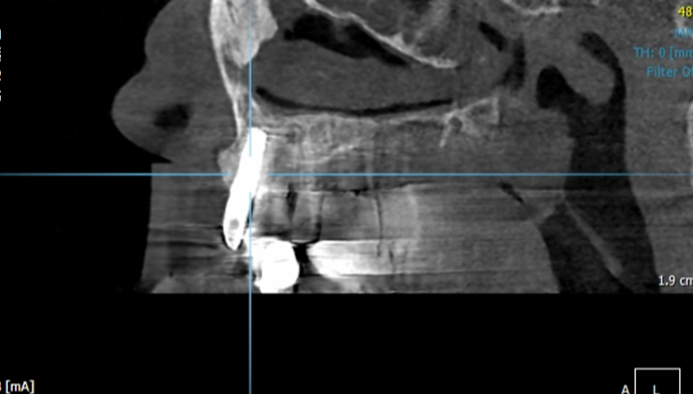

Clinical case: Peri-implantitis treatment case using titanium or NiTi brush

- Courtesy of Dr. Dae-Hee Lee, South Korea -

Dr. Dae-Hee Lee,Maxillary Anterior,Peri-implantitis,Bone regeneration,Aesthetic zone,#21,#22,GBR,Titanium Brush Set